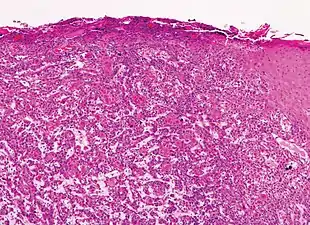

In situ disease

Bowen's disease is essentially equivalent to and used interchangeably with SCC in situ, when not having invaded through the basement membrane.[33] Depending on source, it is classified as precancerous[34] or SCC in situ (technically cancerous but non-invasive).[35][36] In SCC in situ (Bowen's disease), atypical squamous cells proliferate through the whole thickness of the epidermis.[33] The entire tumor is confined to the epidermis and does not invade into the dermis.[33] The cells are often highly atypical under the microscope, and may in fact look more unusual than the cells of some invasive squamous cell carcinomas.[33]

SCC in situ, high magnification, demonstrating an intact basement membrane.[33]